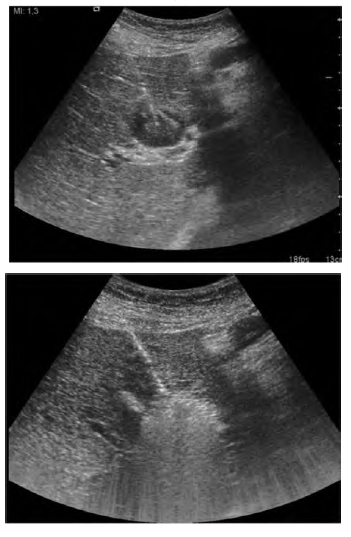

Percutaneous ablation is the best alternative for patients with early-stage HCC who are not eligible for resection or transplant procedures.5 Tumor ablation is achieved by modifying the temperature of neoplastic cells (radiofrequency, microwave, laser, and cryoablation) or by using chemical substances (alcohol, acetic acid).7 The most common techniques are RFA and PEI. Radiofrequency ablation achieves higher rates of complete tumor ablation than PEI. Recurrence rate is higher with PEI treatment. Radiofrequency ablation significantly improves survival and reduces local recurrence compared with PEI, supporting the use of RFA as first-line treatment in patients with small HCC lesions (< 3 cm) and who have well-preserved hepatic function (Figure 2). Percutaneous ethanol injection should be reserved for cases in which RFA is not technically possible (pericholecystic lesions or lesions near the hepatic hilum).11

Figure 2. Percutaneous Radiofrequency Ablation of HCC Lesion